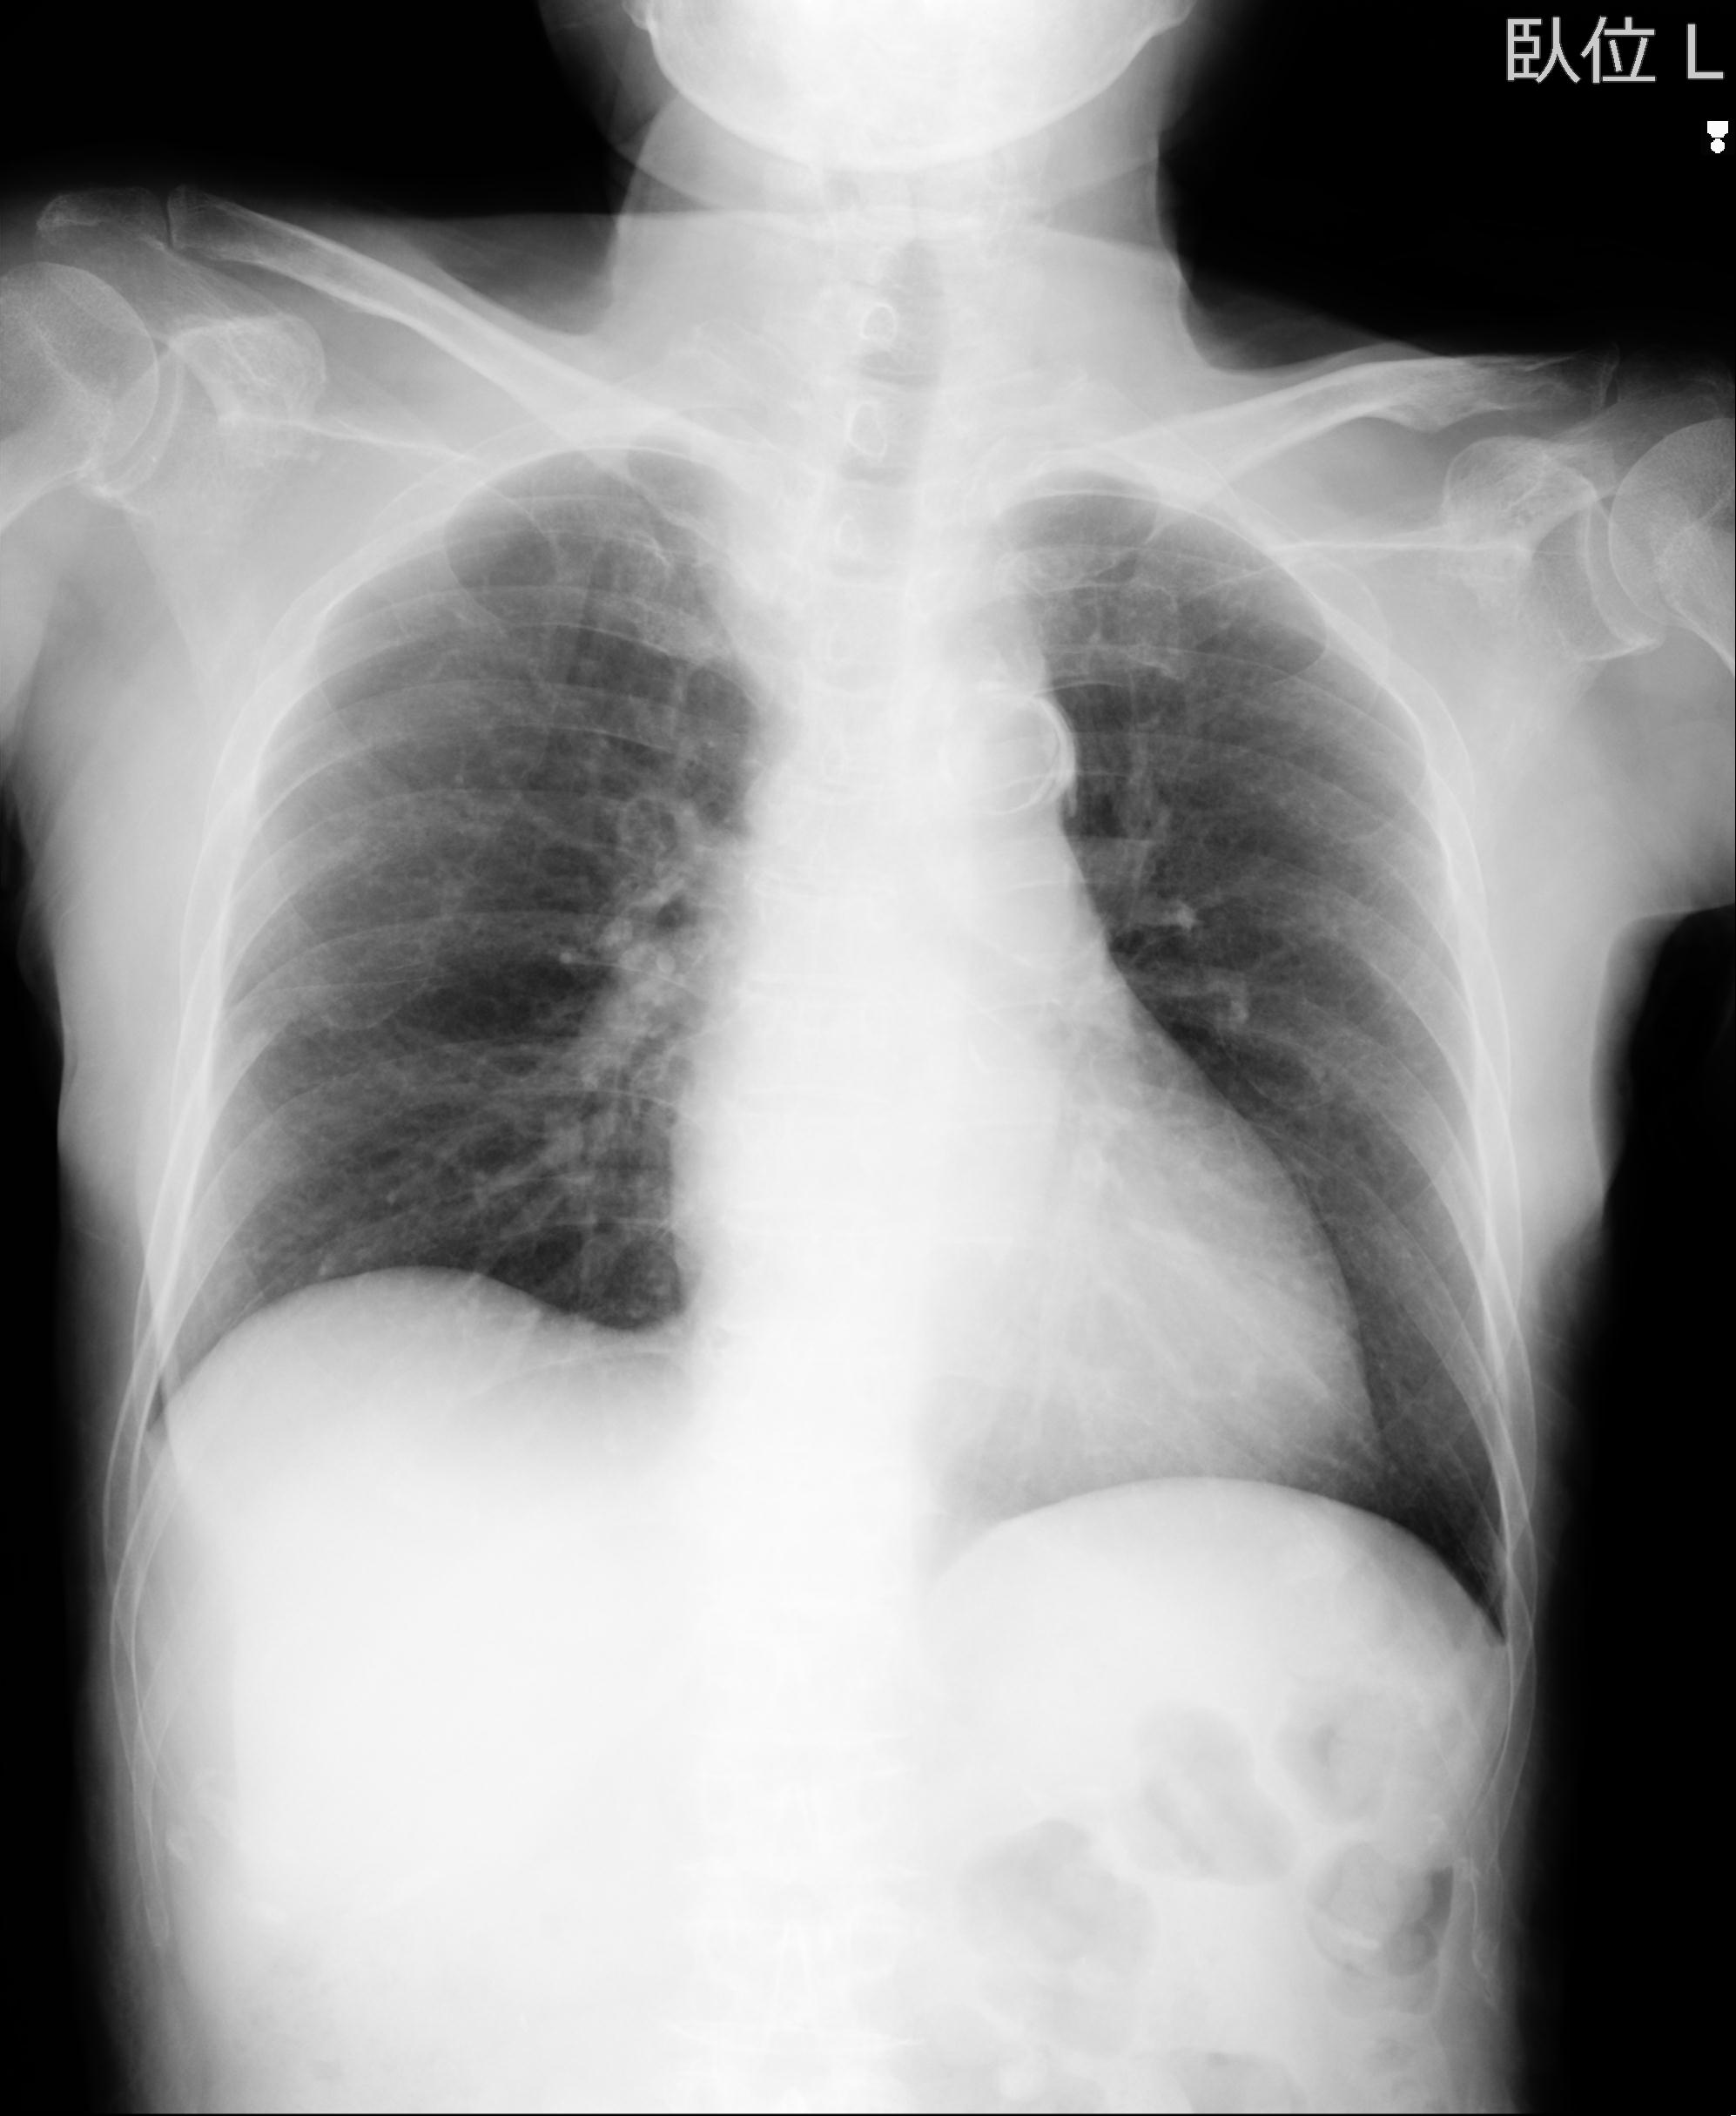

公開写真

症例写真集